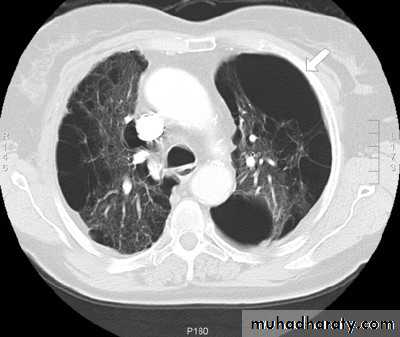

PNX in

Diseased lungDiseases of the Pleura Dr.Mustafa Nema. Baghdad College of Medicine 2013

PNX inCystic lung

disease

CT adds information regarding the presence or absence of pleural fluid and underlying pulmonary disease.Diseases of the Pleura Dr.Mustafa Nema. Baghdad College of Medicine 2013

emphysematous bulla (not PNX)